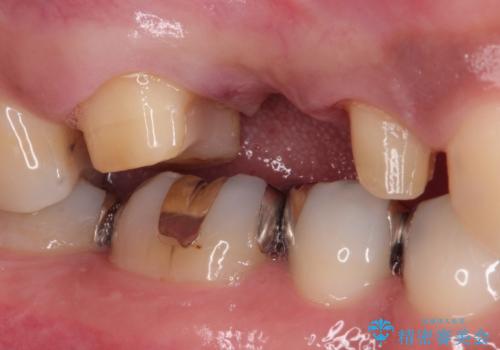

- 他院で治療途中の歯を当院でしっかり治したいとのことで来院されました。

右上のブリッジが途中で切断されて、手前の歯が根の治療の途中でした。

根の治療を行いその後にオールセラミックブリッジを装着する計画となりました。